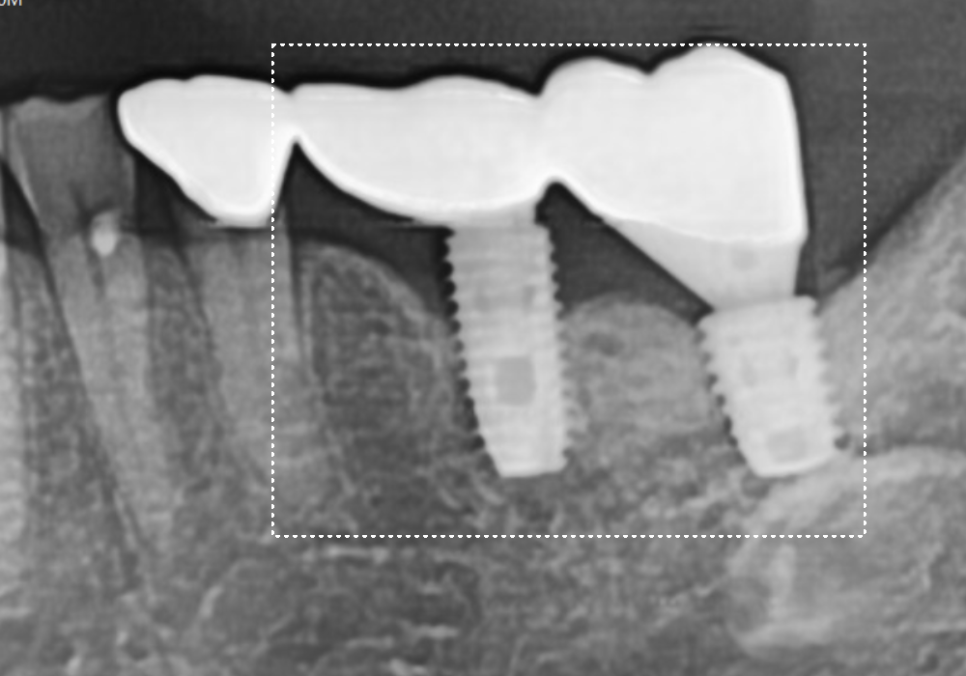

241021

그로부터 2개월 뒤 임플란트와 뼈가

얼마나 잘 결합되었는지 확인해 보았는데요.

다행히 임플란트 뿌리 끝부분까지

잇몸뼈가 아주 튼튼하게

차오른 것을 볼 수 있었습니다.

241202

토대가 완벽하게 만들어진 것을 확인한 후,

기존에 두 임플란트를 하나로 묶고 있던

낡은 보철물을 제거하고

241223

강도와 심미성이 뛰어난

지르코니아 보철물을 새롭게 제작해 드려

치료를 마무리했습니다.